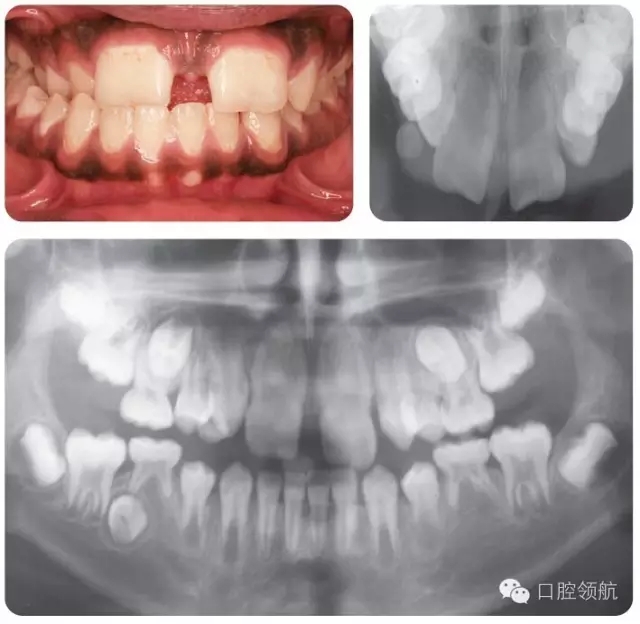

圖2.12中該名15歲男性患者的牙列特征有哪些?

圖2.12

● 上頜中切牙和側(cè)切牙為融合牙。

● LL5缺失。

● UL5,UR5和LR5阻生。

● LLE,ULE和LRE滯留。

● 尖牙和前磨牙的牙根發(fā)育滯后。

圖2.13中的牙列特征有哪些?

圖2.13

● 乳牙列。

● I類切牙關(guān)系。

● 下中線左偏。

● LLB和LLC融合牙。

圖2.14中的牙齒情況如何?

圖2.14

磨牙切牙礦化不全(MIH)——表現(xiàn)為區(qū)域性的釉質(zhì)實(shí)質(zhì)缺陷,在系統(tǒng)發(fā)育時(shí)影響一顆或多顆恒磨牙,伴或不伴切牙損害。